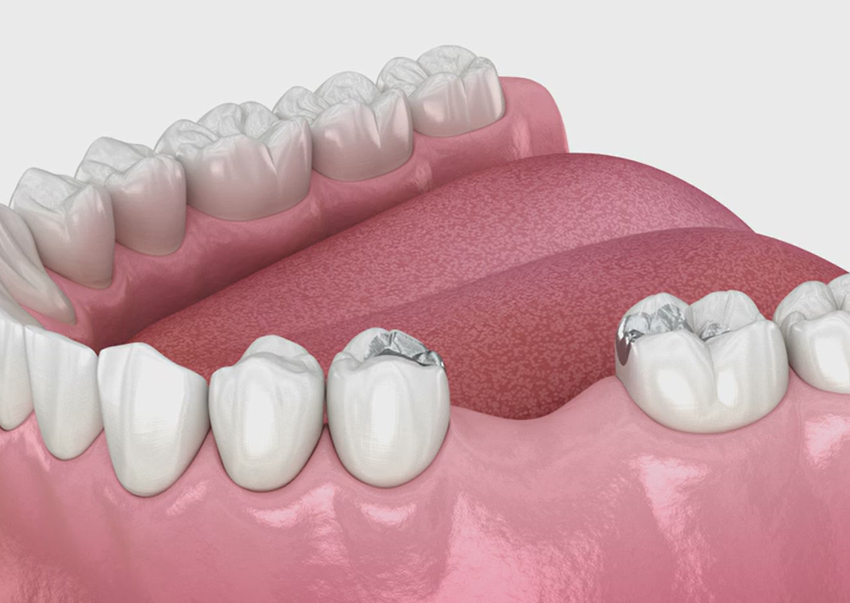

When there is a gap created by one or more missing teeth, bridges are attached to the adjoining natural teeth to fill the gap. Bridges work best for those who have only a few missing teeth. With a fixed bridge, the artificial tooth (known as a pontic) is anchored to new crowns attached to the teeth on both sides of the gap.

It requires two to three visits to complete the treatment.

1. Missing one tooth

2. Reshaping adjacent tooth

3. Reshaping adjacent tooth

4. Bridge is cemented